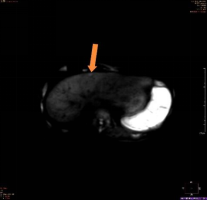

(图3)

上图为一名53岁男性,乙肝、肝硬化随访复查,AFP及超声检查均为阴性;图1为腹部CT平扫显示,肝左叶体积增大,肝实质内未见明确异常密度结节及肿块;图2、图3分别为磁共振平扫T2WI、弥散成像显示,肝左内叶上段见一直径为0.8cm的稍高信号结节(箭头所示);图4为T1WI增强动脉期显示,该结节动脉期高强化(箭头所示);该病人为肝癌高危人群,磁共振扫描高度怀疑此异常信号结节为早期小肝癌,患者遂到上级医院手术,术后病理证实为肝细胞肝癌。